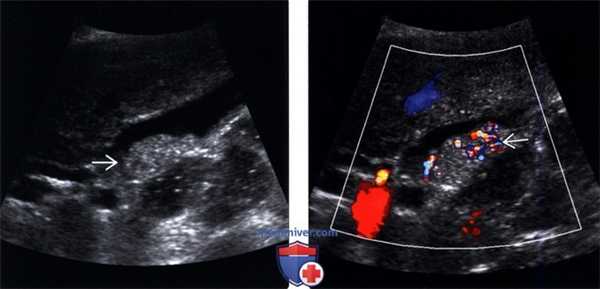

(Левый) Положение пациента на боку. На продольном УЗ срезе визуализируется смещающийся книзу под действием гравитации эхогенный сладж, формирующий сгусток.

(Правый) На продольном УЗ срезе у этого же пациента в положении на боку определяется смещающийся книзу под действием гравитации эхогенный сладж, также виден «мерцающий» артефакт.